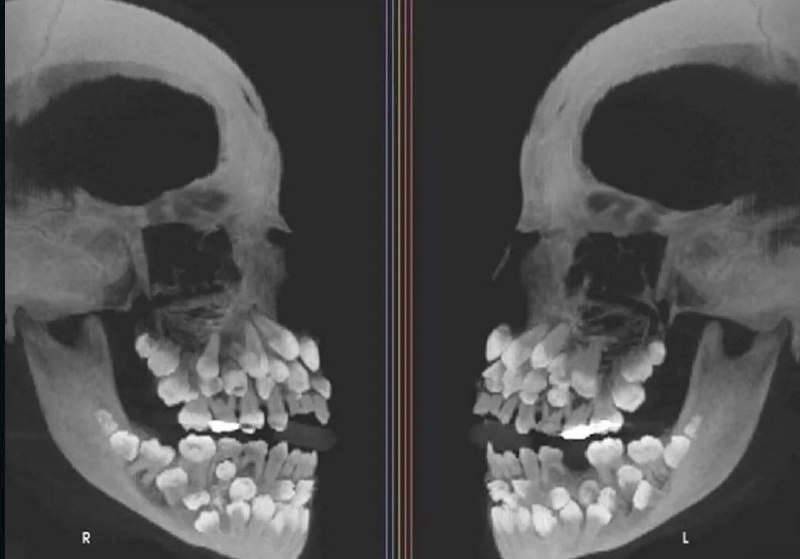

На рентгеновском снимке изображён пациент, страдающий гипердонтией — это редкое состояние, при котором у человека формируется чрезмерное количество зубов. В большинстве случаев при гипердонтии выявляют лишь 1–2 лишних зуба, однако в данном случае были обнаружены целых 81 зуб, что значительно превышает норму в 32 зуба. Плюс ещё одна фобия.